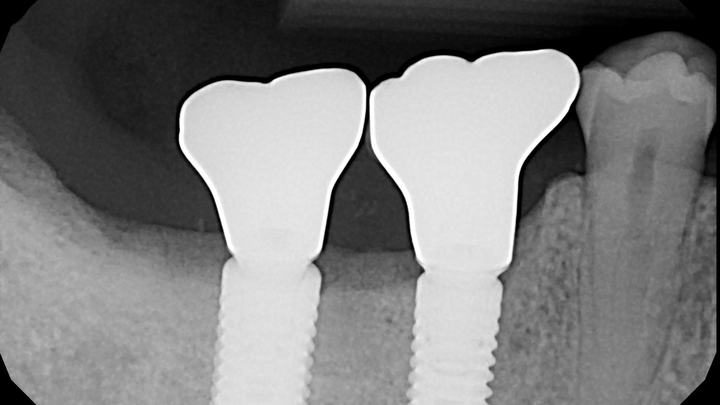

Two dental implants I got five years ago that enable me to chew on the right side of my mouth failed this year. In June 2025, I was billed $2,721 for replacement of the abutment (screw) and crown on one implant. In September 2025, I was billed an additional $1,656 for removal of the other implant and for a bone graft due to a gum infection that impacted the foundation of this other implant.